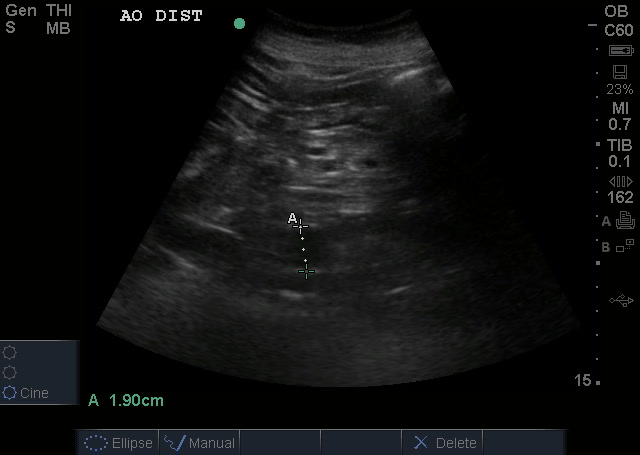

The Tank: IVC for volume status

IVC is slightly on the low/normal – (normal measurement being 1.5-2.5 cm with no more than 50% respiratory variation). Not seen is the complete collapse that occurred with sniff.